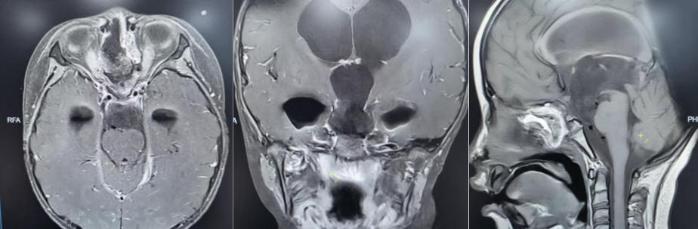

为精准掌握肿瘤情况,团队为欢欢完善了垂体MRI平扫+增强检查及相关激素水平检测。结果显示:肿瘤体积超过4厘米,形如鸡蛋,已严重压迫视神经与垂体,突入第三脑室,并与周围重要神经血管结构紧密粘连。

手术中,团队借助高清4K神经内镜,细致分离肿瘤与周围神经、血管的粘连。历经3小时,肿瘤被完整切除,下丘脑、垂体柄、视神经等重要结构均得到完好保护。术后病理确诊为颅咽管瘤。

在医护团队的精心照护下,欢欢神经功能障碍明显改善,视力逐渐恢复,头痛症状完全消失,梗阻性脑积水得到有效缓解。之后顺利拔除脑室引流管,未出现脑脊液漏、感染等并发症,内分泌功能也通过药物获得精准调控。